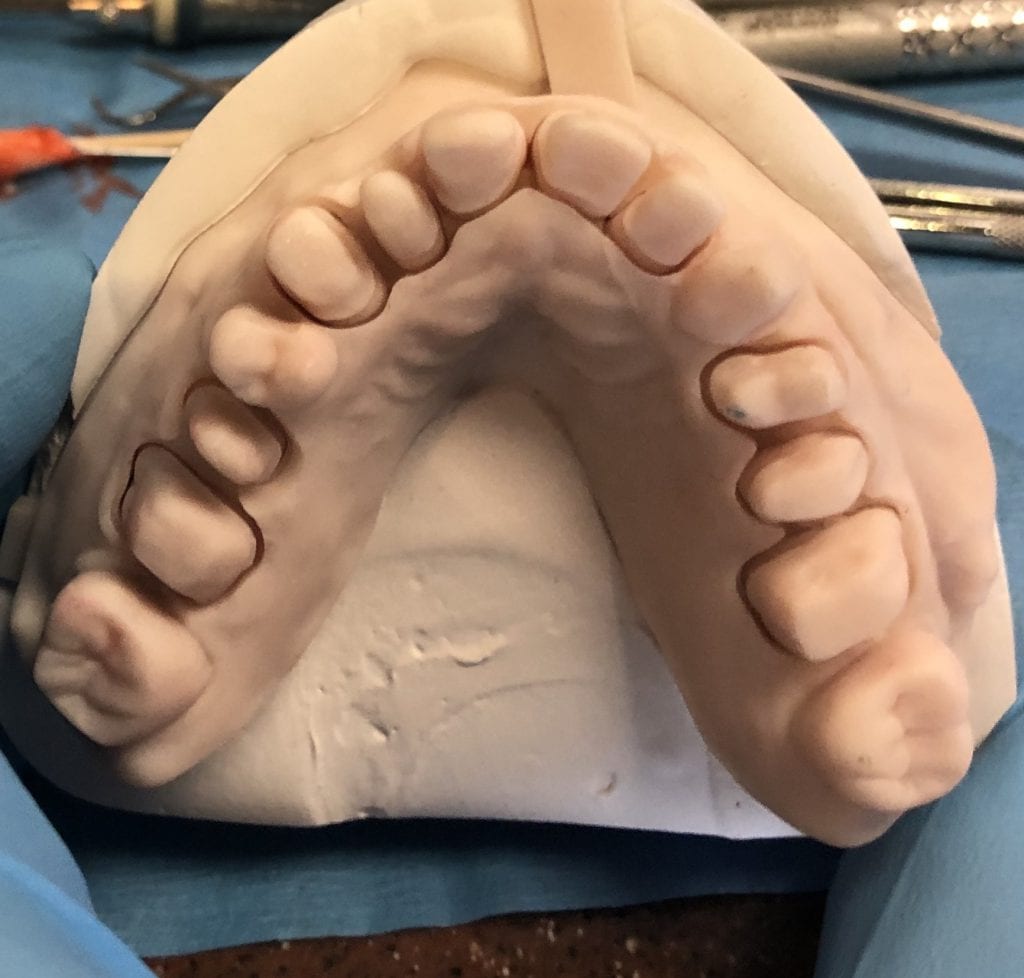

Anterior preps scanned along with the opposing and the initial bite

segmental imaging to building a master model

upper and lower models related to each other for design